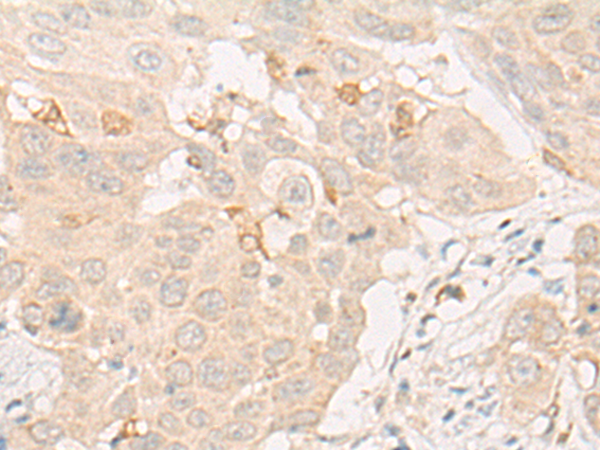

ELISA, IHC |

IHC Positive control: |

Human liver cancer;Human esophagus cancer |

IHC Recommended dilution: |

20-100 |